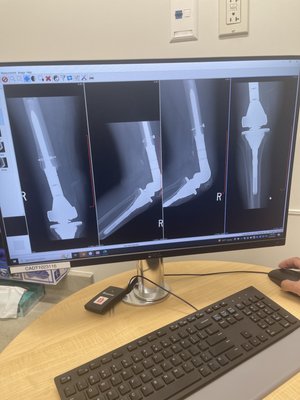

Rana Robotic Knee Replacement Sumit Rana Md Robotic knee replacement utilizes a detailed ct scan to map out your knee. we then create a 3d model and a very specific plan for surgery. during the procedure, dr. rana utilizes the latest robotic technologies as a tool for precision and accuracy in his knee replacement procedures. His practice is focused on hip and knee replacement surgery, including: partial and total knee replacements, anterior and posterior hip replacements, knee arthroscopy, orthopedic trauma and fracture care, and revising hip and knee replacements that have failed.